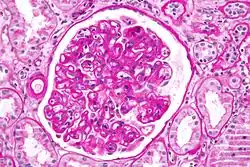

Diagnosis of acute rejection relies on clinical data—patient signs and symptoms but also calls on laboratory data such as blood or even tissue biopsy. The laboratory pathologist generally seeks three main histological signs: (1) infiltrating T cells, perhaps accompanied by infiltrating eosinophils, plasma cells, and neutrophils, particularly in telltale ratios, (2) structural compromise of tissue anatomy, varying by tissue type transplanted, and (3) injury to blood vessels. Tissue biopsy is restricted, however, by sampling limitations and risks/complications of the invasive procedure.[31][32][33] Cellular magnetic resonance imaging (MRI) of immune cells radiolabeled in vivo might—similarly to Gene Expression Profiling (GEP)—offer noninvasive testing.[34][35]